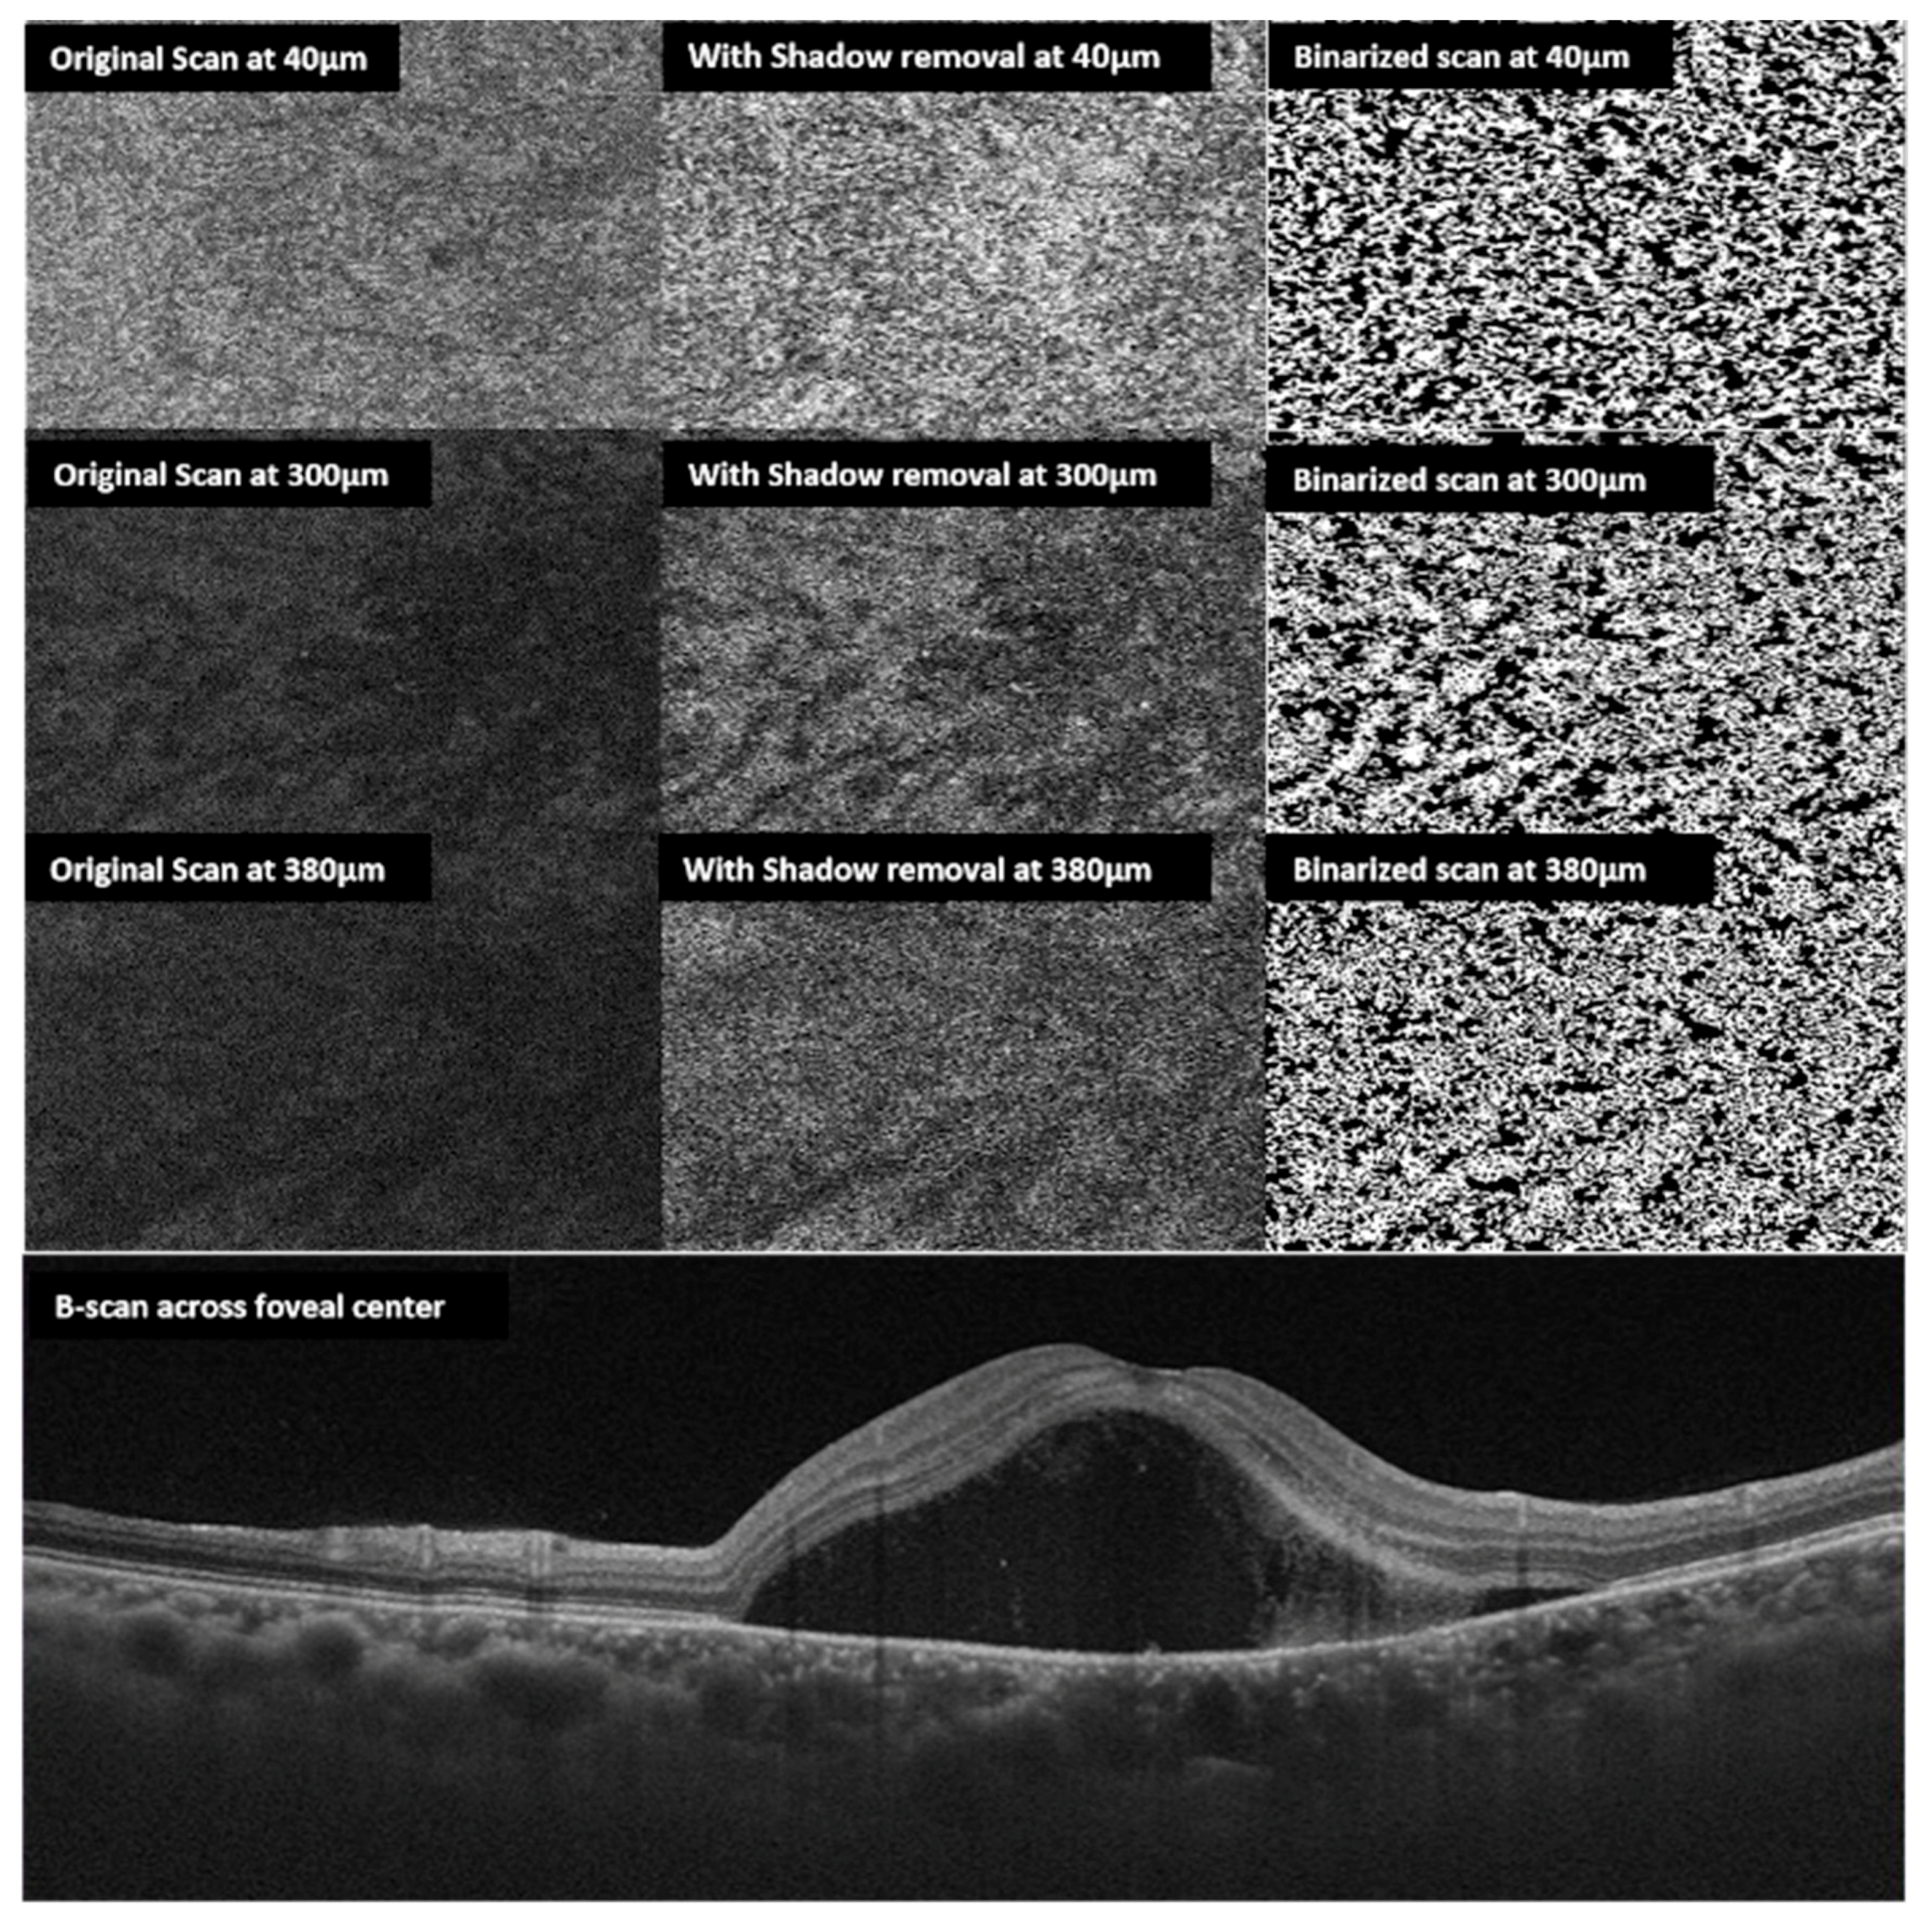

En Face Choroidal Vascularity in CSCR

- Wong, R.L.; Singh, S.R.; Rasheed, M.A.; Goud, A.; Chhablani, G.; Samantaray, S.; AnkiReddy, S.; Vupparaboina, K.K.; Chhablani, J. En-face choroidal vascularity in central serous chorioretinopathy. Eur. J. Ophthalmol. 2020, 2020. [Google Scholar] [CrossRef]